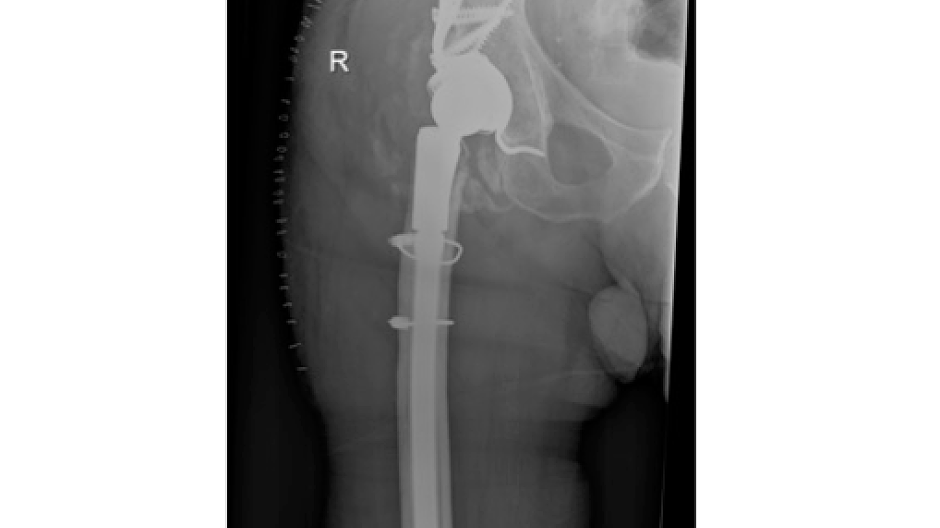

Fotos Unfallchirurgie und Orthopädie